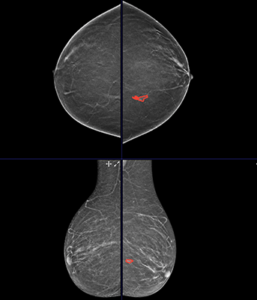

This annotation protocol was designed to create a high-quality, radiologist-validated dataset for breast imaging analysis using mammography and digital breast tomosynthesis (DBT). The annotation process was report-guided and performed by trained radiologists to ensure accurate lesion localization, segmentation, and structured characterization.

The primary objective of the protocol was to extract detailed lesion-level and study-level information from radiology reports and accurately map these findings onto corresponding imaging data through structured classification and pixel-level segmentation.

All lesions described in the radiology report were identified on mammography and tomosynthesis images.

For each lesion:

This ensured accurate lesion localization and spatial consistency across imaging datasets.

In addition to segmentation, detailed structured classification was performed at both the study and lesion levels.

Lesion-Level Classification

Each annotated lesion was characterized using structured metadata fields, including:

Lesion IDs were maintained consistently across mammography and tomosynthesis images to ensure cross-modality consistency.